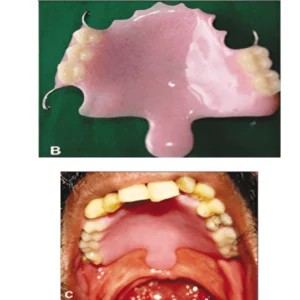

Intra-oral prosthesis is a special dental appliance designed to replace missing oral structures, support speech, help feeding, reduce dryness, and restore facial balance after surgery, injury, or birth conditions.

Feeding Aid Prosthesis

A dental device used to close a large opening or defect in the hard and/or soft palate that creates a communication between the oral and nasal cavities.